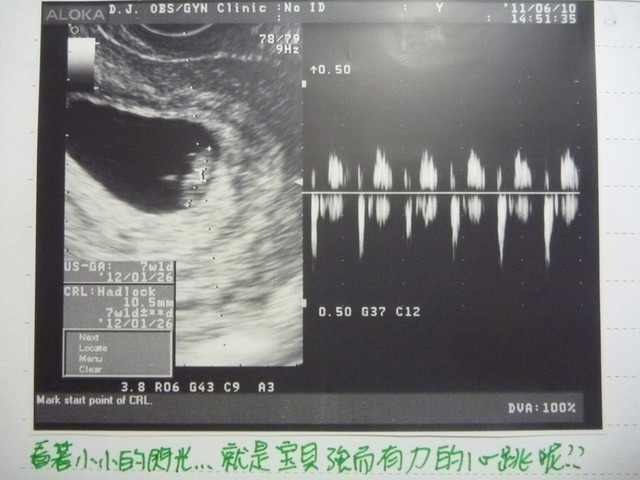

今日估約7週1天~

預產期提前一天~押在2012/01/26~

小貝果有心跳囉!!

今天小貝果長約1.05cm~